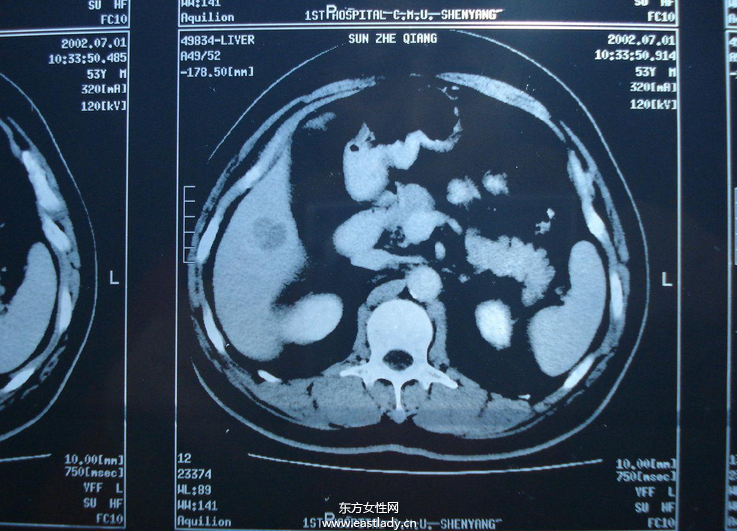

中晚期肝癌介入治疗的方法有哪些

所谓肝癌介入治疗,是指经过股动脉插管将抗癌药物或栓塞剂注入肝动脉的一种区域性局部化疗,它是目前非开腹手术治疗肝癌的首选治疗方法,疗效已得到肯定,是中晚期肝癌治疗最佳手段。

其主要原理是采用局部靶向药物灌注、肿瘤血管栓塞及氩氦冷冻消融等方式集中杀灭肿瘤细胞,最大限度地降低肿瘤负荷,可逆转部分患者肝癌分期,使不能切除的肝癌病例转化为可切除的肝癌病例。